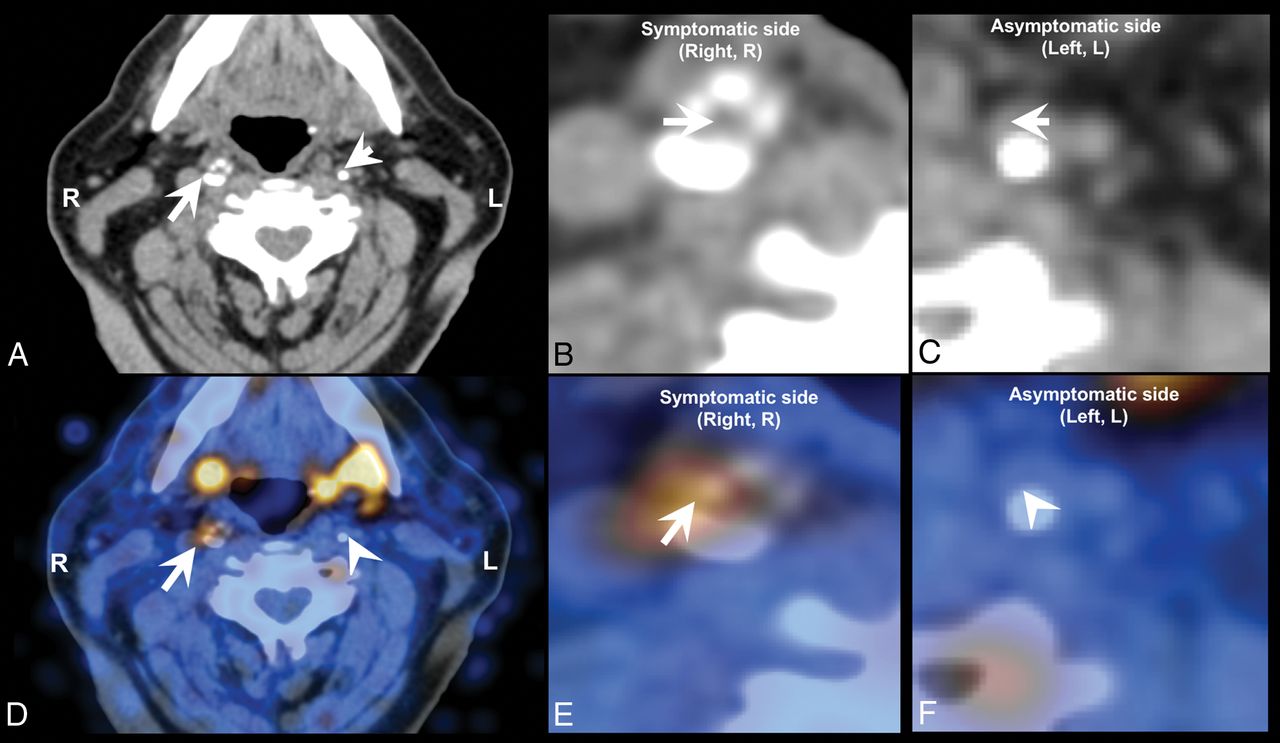

A wide variety of studies has assessed the diagnostic potential of nuclear medicine techniques for imaging and quantifying plaque inflammation, such as by PET using the widely available [18F] FDG or newer radiotracers such as [18F] fluorocholine (Fig 10).206⇓–208 Nuclear medicine tracer techniques have also shown efficacy in the identification of neovascularization.209,210

[18F] fluorocholine positron-emission tomography CT (18F-FCH PET CT) image of a symptomatic (arrow) and contralateral asymptomatic (arrowhead) carotid plaque of a patient who experienced right-sided stroke. A, Diagnostic contrast-enhanced CT shows a significant stenosis in the right internal carotid artery because of a calcified plaque, whereas a noncalcified atherosclerotic plaque can be seen on the contralateral internal carotid artery. B, CT, inset on the symptomatic plaque. C, CT, inset on the asymptomatic plaque. D, The fused PET CT image denotes a focal area of high [18F] FCH uptake in the right symptomatic carotid plaque, whereas there is no visible [18F] FCH uptake in the left asymptomatic carotid plaque. E, Fused PET CT, inset on the symptomatic plaque. F, Fused PET-CT, inset on the asymptomatic plaque.

Because vulnerable plaques are infiltrated by lymphocytes and macrophages, with the latter cell population capable of taking up [18F] FDG from the interstitial spaces, [18F] FDG PET can be used to directly detect plaque inflammation in various anatomic locations.211 In recent years, a number of studies have assessed the diagnostic potential of [18F] FDG PET to image and quantify plaque inflammation206,207 as well as monitoring the reduction of plaque inflammation resulting from statin therapy.208